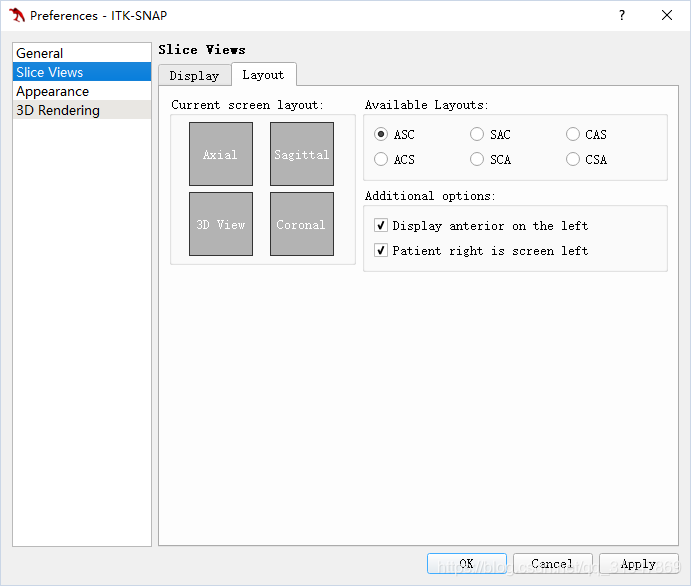

调整切片的顺序:

SNAP 默认显示顺序为:左上角为轴向切片(axial),右上角为矢状切片(sagittal),右下角为冠状切片(coronal),可以根据习惯更改显示顺序:

Tools -> Preference -> Slice Views -> Layout